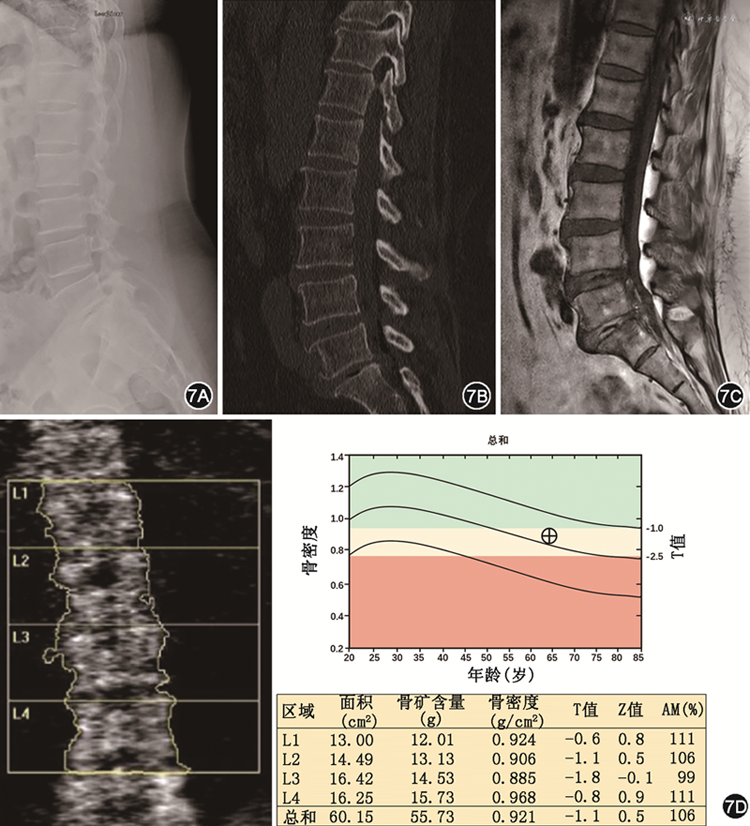

目前常用的几种骨密度影像学检测方法均在一定程度上对早期发现骨质疏松症高危者具有提示意义,同时也各有欠缺,故临床上需依患者情况选择适宜的检测方法。X线片、常规CT、MRI及DXA检测结果的比照见图7。

注:AM年龄匹配